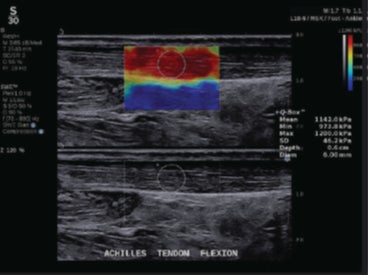

(2)進化したSWE PLUS™イメージング

従来システムではSWEのレンジは800 kPaまででしたが、SUPERSONIC™ MACHシリーズでは、最大1200 kPaまで測定が可能*となっています。

*MSKプリセット使用時

整形領域では腱や筋肉の硬さ、乳腺領域では腫瘍の硬さ、肝臓領域では、肝組織の硬さを評価することで、疾患の早期診断に貢献します。